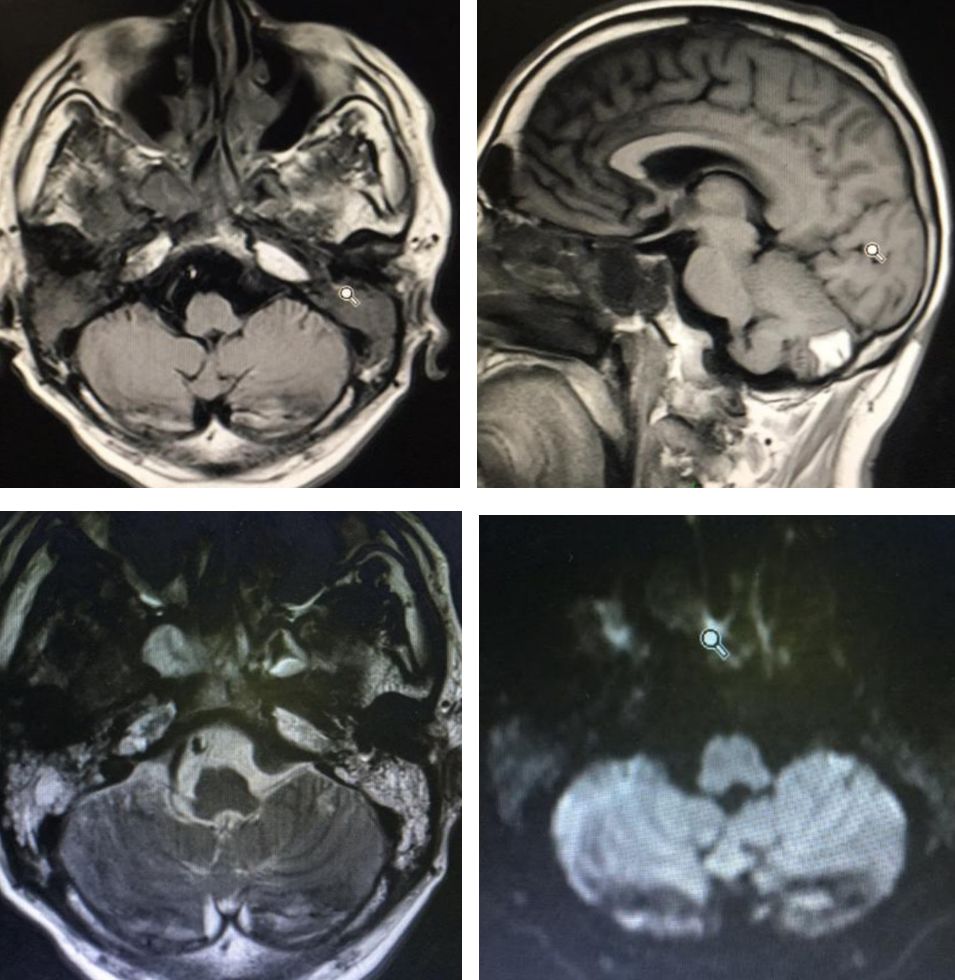

病例10

女性,52岁。头痛、恶心、呕吐4小时入院,既往有高血压、糖尿病。

答案:烟雾病。

好多老师认为脑室出血,不理解为什么是烟雾病。患者本次入院行MRA及CT平扫图像如下:

烟雾病和烟雾综合征的临床表现复杂多样。脑缺血最为常见,可表现为短暂性脑缺血发作(transient ischemic attack,TIA)、可逆性缺血性神经功能障碍(reversible ischemic neurologic deficit,RIND)或脑梗死,其中TIA常由情绪紧张、哭泣、剧烈运动或进食热辣食物等诱发。自发性颅内出血多见于成年患者,主要原因是烟雾状血管或合并的微动脉瘤破裂出血,以脑室内出血或脑实质出血破入脑室最为常见,也可见基底节区或脑叶血肿,单纯蛛网膜下腔出血较少见。神经功能障碍与脑缺血或颅内出血部位等相关。其他临床表现还包括认知功能障碍、癫痫、不随意运动或头痛等。